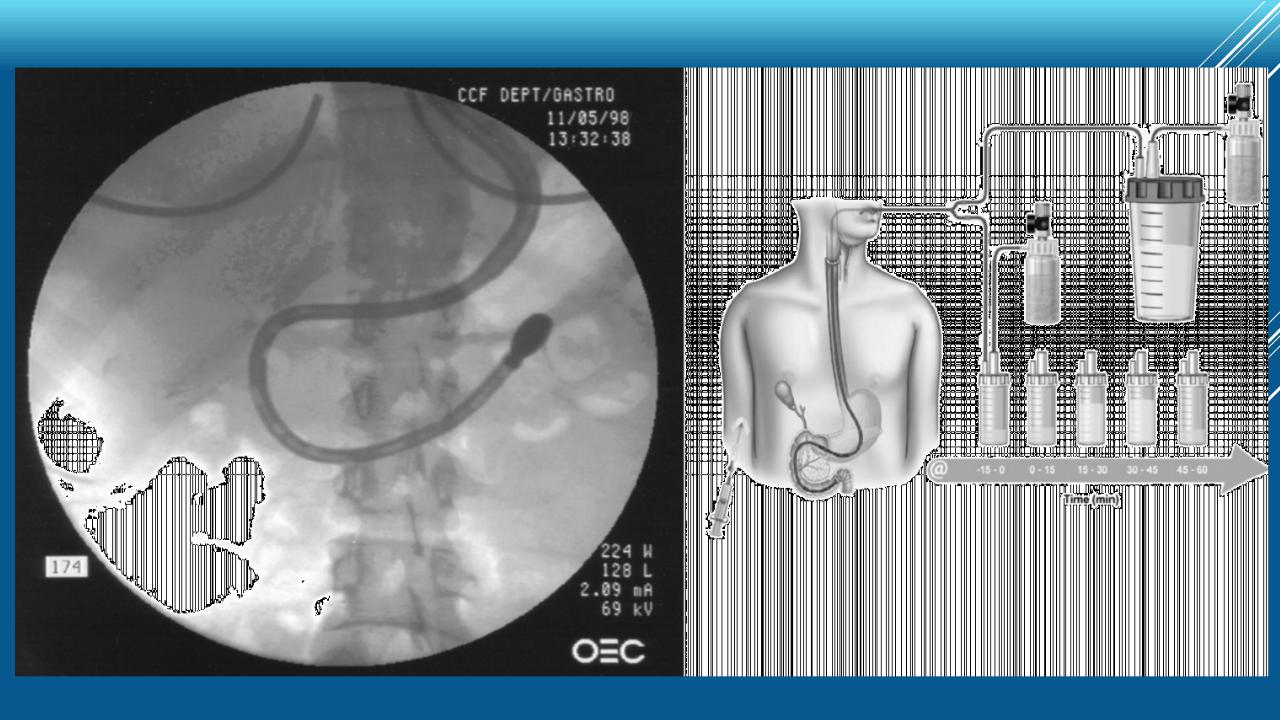

Хронический панкреатит: диагностика

DL Cionwell et al. Pancreas. 2014;43(8):1143-62 Majumder S, Chari ST.. Lancet. 2016 7;387(10031):1957-66.